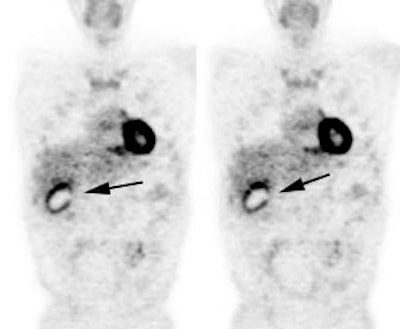

Vascular graft activity: The patient below had a prior graft repair of an ascending aortic aneurysm. Tracer uptake can be seen in the ascending aortic graft (black arrows). The patient also has a left upper lobe lung cancer (red arrows). |

|